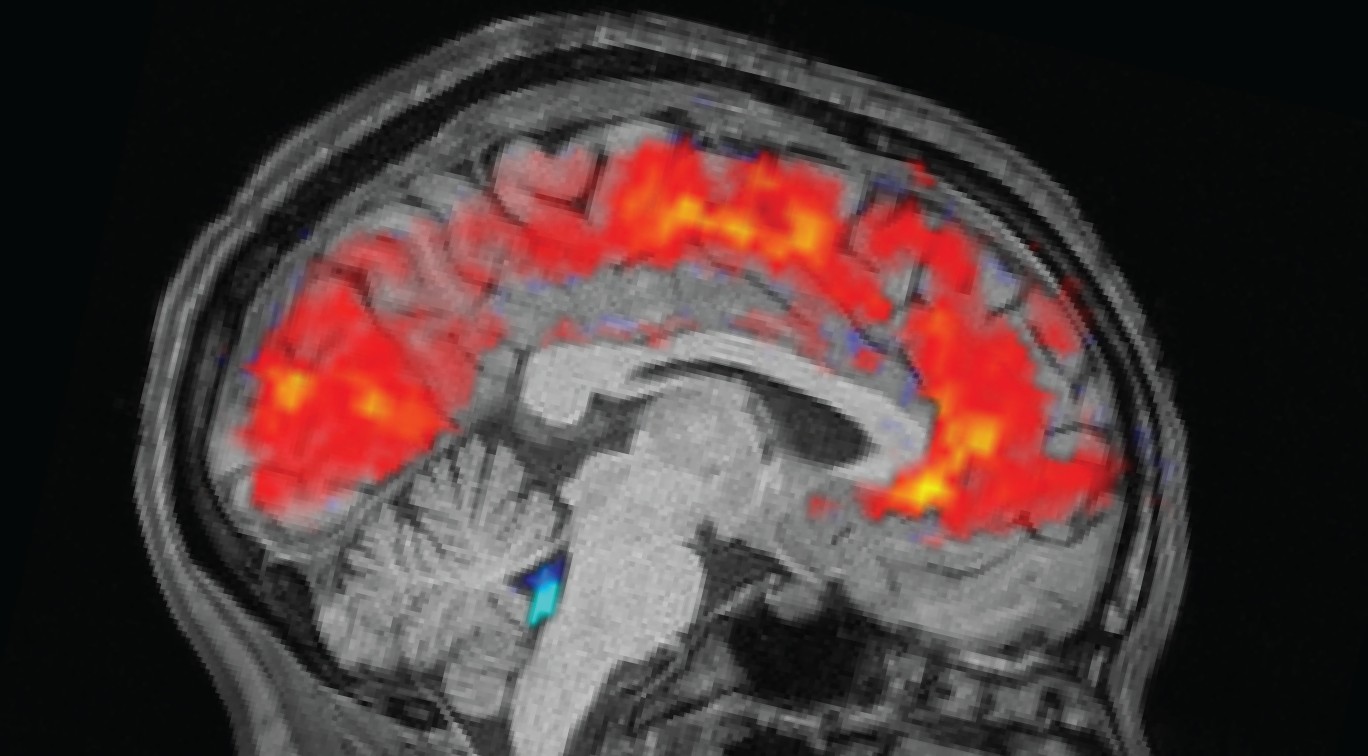

Исследование, проведенное учеными из MIT, отслеживало 26 здоровых взрослых как в хорошо отдохнувшем, так и в лишенном сна состоянии. Участники, которых держали без сна всю ночь, демонстрировали большие импульсы СМЖ, циркулирующей в их мозге, совпадающие с периодами невнимательности. Этот скачок жидкости, обычно связанный с глубокой стадией медленного сна (non-REM), был напрямую связан с изменениями размера зрачков: расширение перед невнимательностью, сужение по мере возвращения концентрации. Команда использовала электроэнцефалографию (ЭЭГ) и функциональную магнитно-резонансную томографию (фМРТ), чтобы сопоставить эти изменения в реальном времени, показывая, что провалы внимания — это не просто замедление нейронной активности; это движение жидкости.